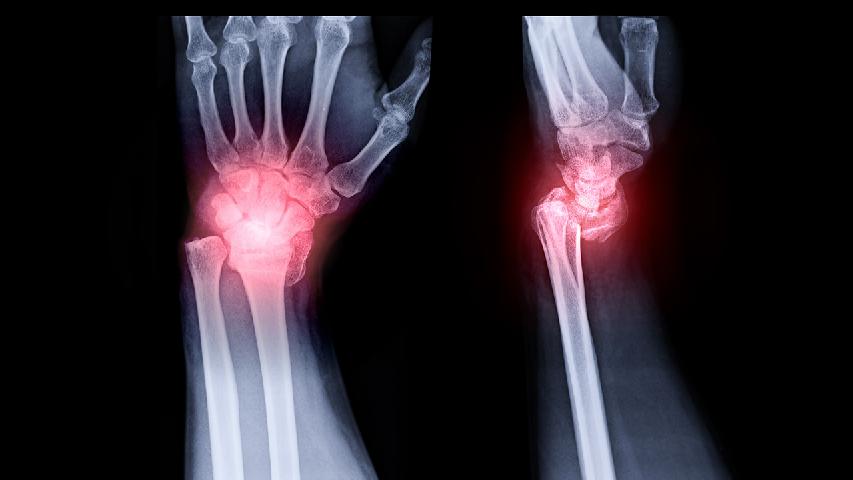

半月板损伤多由于膝部剧烈而突然的扭伤所致。多发于青年,尤其是搬运工、足球与篮球运动员及其他强体力劳动或运动的人。年轻人在运动的时候,如果不小心或者强度过大造成对膝盖的伤害,很容易造成半月板损伤。有些人长期下蹲位工作,亦可造成外侧半月板慢性损伤。半月板损伤多有明显外伤史。主要症状是膝关节疼痛。患者会出现剧烈疼痛,关节肿胀,屈伸活动功能的障碍,还可出现膝部打软腿现象。其次,当伸屈膝关节,膝部出现弹响声。造成日常生活的严重不便,因此应尽早采取治疗措施,切莫延误。

当半月板损伤的时候,切忌病急乱投医,找准对的治疗办法才是关键。手术是治疗半月板损伤的主要方法。过去认为半月板无修复能力,半月板撕裂可导致创伤性关节炎,切除半月板无损于膝关节的功能。但近期研究证实,膝关节半月板承受通过膝关节的相当一部分载荷。远期手术疗效分析还表明,切除半月板可导致后期膝关节退变。因此对半月板的手术适应证应慎重权衡。